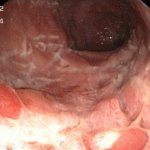

Для точного диагноза могут потребоваться дополнительные исследования органов брюшной полости, такие, как компьютерная томография, МРТ, рентгенография органов, ультразвуковое исследование или эндоскопия.